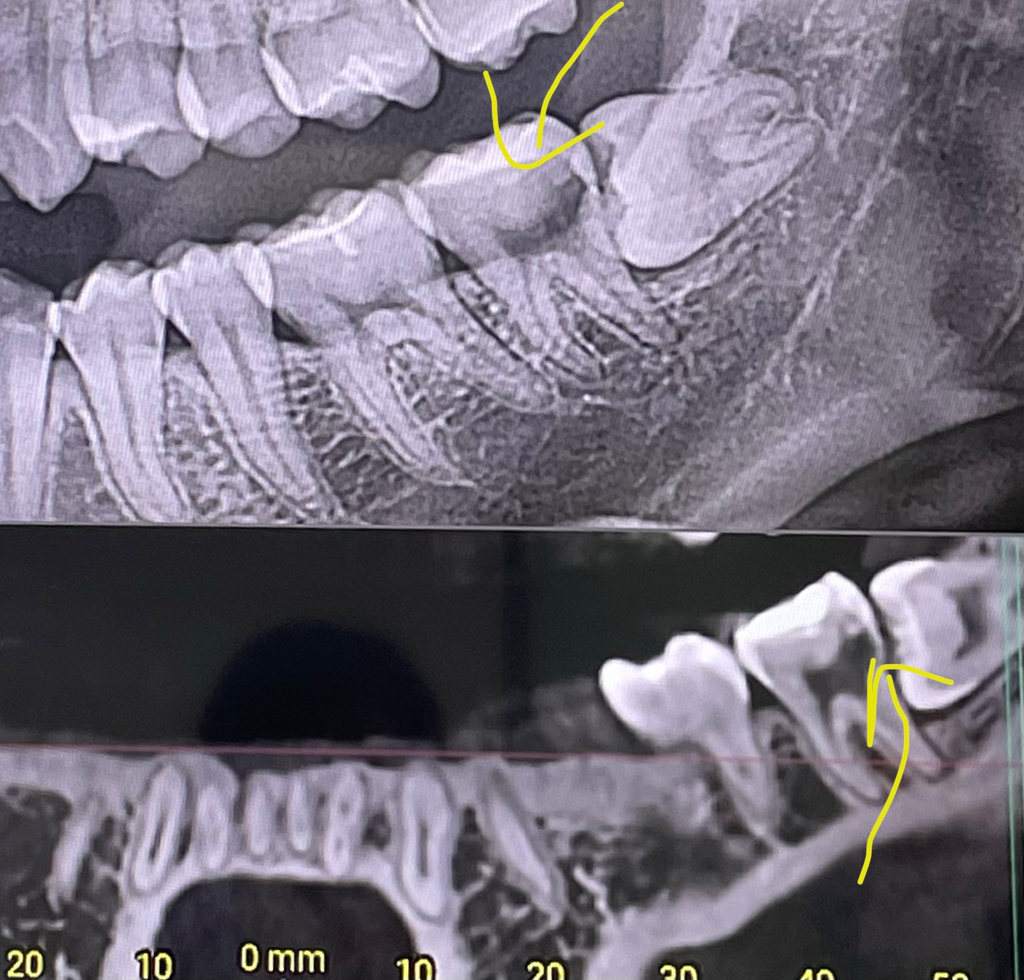

제가 6개월마다 치과 진료를 받다가 갑자기 충치의심된다며 ct를 찍었습니다 저기 검정색으로 보이는 부분이 충치라고 신경치료까지 해야한다고 했어요 그래서 다른 치과 두곳을 더 가봤는데 충치가 없다고 해서 그냥 두고 사랑니만 뽑았습니다

사랑니 뽑은지 2달이 됐는데 갑자기 저기 신경치료 해야한다했던 치아가 조금 아프네요 가만히 있으면 안아픈데 뭐 씹거나 하면 약간 통증이 있어요 사랑니 발치 후 후유증이 갑자기 나타난건가요 아니면 정말 신경치료를 해야하는건가요 ? ㅜㅠ

사랑니뽑기 전에는 사랑니에 가려서 충치가 안보일 수있지만, 현재 사랑니를 발치하였다면 충치가 있는지 어느정도 정확히 보일것입니다.

사랑니 때문에 안좋은 부위에 충치가 생기신거 같습니다. 부위도 안좋고 충치도 신경에 가까워 보이네요. 신경치료를 하셔야될것같습니다.

사랑니가 기울어져 있어서 해당부위에 음식물이 오래 저류 되어 있었다면 충치가 생길수 있습니다.

또한 후방에 사랑니가 제거되어 어금니를 지탱하고 있는 치조골이 업어져서 불편감이 생길수도 있어요.